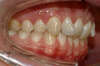

Vues après le traitement